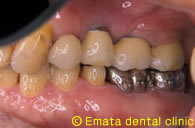

上顎の入れ歯があわない。自分の歯のように食べたい。

Before

After